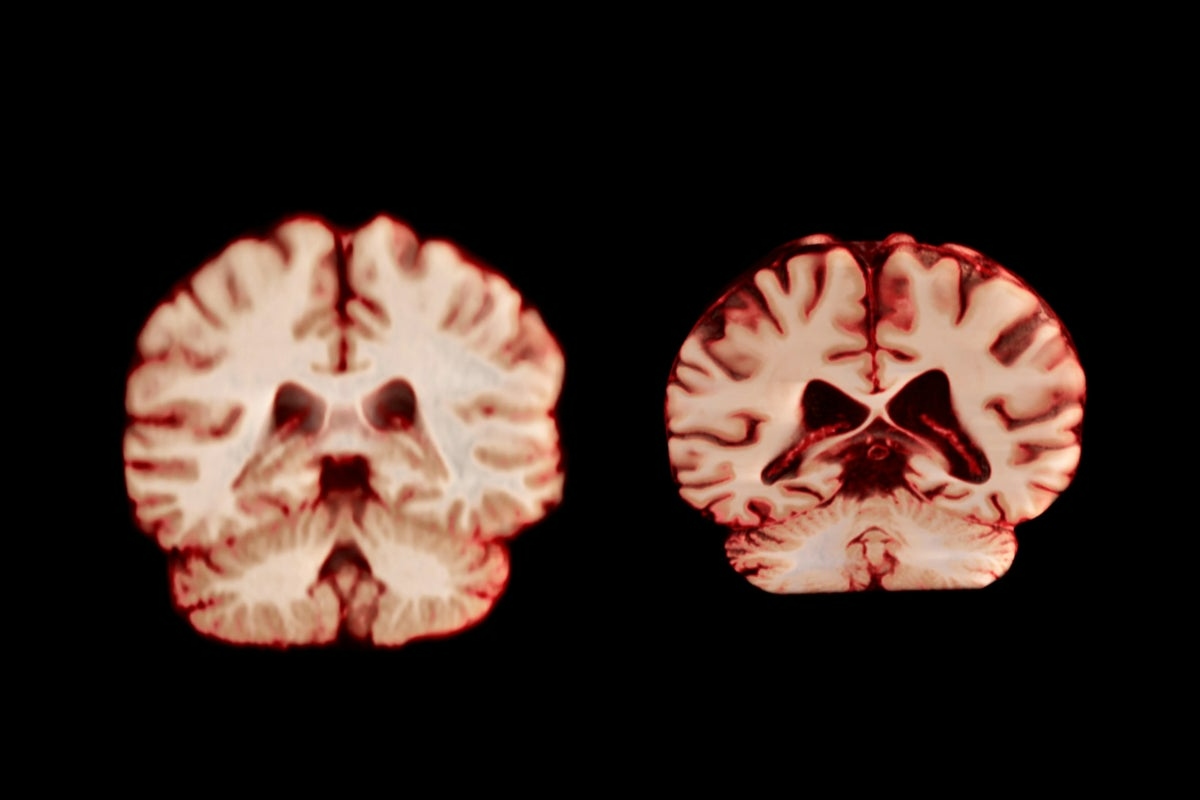

Smanjenje volumena mozga i brzina obrade

Riječ je o postupnom procesu koji počinje desetljećima ranije, ali se ubrzava nakon sedamdesete. Prefrontalni korteks, regija koja nam omogućuje planiranje, donošenje složenih odluka, kontrolu impulsa i održavanje pažnje, jedno je od najpogođenijih područja. Također, promjene trpi i bijela tvar, odnosno živčana vlakna obavijena mijelinom koja povezuju različite regije mozga. Mijelin, zaštitni sloj koji omogućuje električnim impulsima da brzo putuju između neurona, počinje propadati.

Potrebno je više vremena za obradu novih informacija, brze razgovore postaje teško pratiti, a riječ koju želimo izgovoriti često nam je „na vrhu jezika“, ali ne dolazi. „To nije nedostatak inteligencije, to je promjena u brzini obrade podataka“, tvrdi stručnjakinja. Nakon sedamdesete, hipokampus počinje raditi drugačije. Ne gubi svu sposobnost pamćenja, ali postaje selektivniji i sporiji. Možete se s emocionalnom jasnoćom sjetiti nečega što se dogodilo prije pedeset godina, ali ime osobe koju ste sreli jučer ili mjesto gdje ste jutros ostavili ključeve mogu ispariti poput dima.